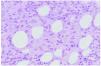

La paniculitis eosinofílica, caracterizada por la infiltración septal o lobular del tejido adiposo por un gran número de eosinófilos (en la mayoría de casos más de 25 eosinófilos por campo de gran aumento) (fig. 4), se ha identificado en pacientes con una gran variedad de condiciones clínicas asociadas22,23. Así, para algunos autores, más que una entidad individualizada, la paniculitis eosinofílica sería un peculiar patrón histopatológico de paniculitis común a varias enfermedades24. El espectro clínico de lesiones cutáneas con cambios histológicos de paniculitis eosinofílica tiene como expresión más común las lesiones nodulares, aunque también incluye úlceras, pápulas y placas urticariales, púrpura, vesículas y pústulas, si bien todas ellas con un componente nodular subcutáneo añadido23. Las enfermedades asociadas con mayor frecuencia a paniculitis eosinofílica son la gnathostomiasis (lo que se ha conocido como paniculitis nodular migratoria eosinofílica), la vasculitis leucocitoclástica, el eritema nudoso y las picaduras de artrópodo. En ocasiones los eosinófilos infiltran también la dermis suprayacente con un aspecto histológico idéntico al de la celulitis eosinofílica de Wells e, incluso, la epidermis con aspecto de espongiosis eosinofílica23.

Fig. 4.--Paniculitis eosinofílica por picadura de artrópodo.

Se han descrito ejemplos de paniculitis eosinofílica como reacción local a una causa claramente identificable (picaduras de artrópodo, granulomas por inyección, medicamentos)23,25,26, si bien en la mayoría de los pacientes existe algún proceso cutáneo o sistémico asociado como dermatitis atópica y de contacto22,27, eritema nudoso22, celulitis eosinofílica de Wells22, enfermedades psiquiátricas (paniculitis facticia)22,28, diabetes29, enfermedades tiroideas22, infecciones (estreptococias, gnathostomiasis, toxocariasis, fascioliasis hepática)30-35, parotiditis recurrente36, vasculitis (vasculitis leucocitoclástica, poliarteritis nudosa)23, síndrome de Sjögren, paniculitis lúpica, morfea profunda, enfermedades hematológicas (leucemias, linfomas T y B, anemia refractaria con exceso de blastos) y neoplasias sólidas22,23.

Parece, pues, que la paniculitis eosinofílica es un hallazgo histológico poco específico que, no obstante, debe reconocerse con el fin de proceder a realizar los pertinentes exámenes clínicos y de laboratorio que permitan descartar las posibles enfermedades cutáneas y sistémicas asociadas24.